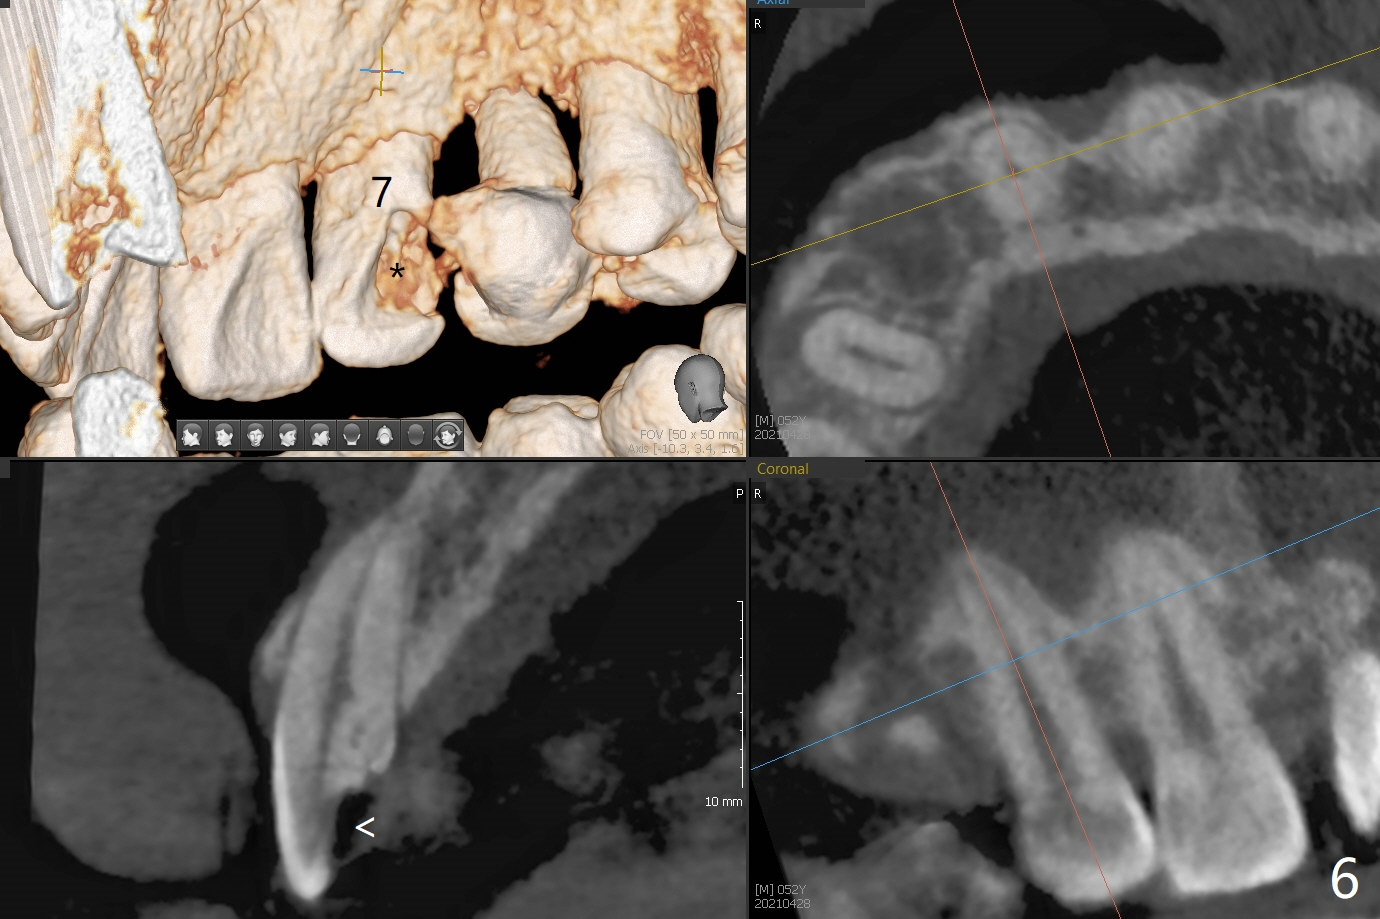

A 52-year-old man requests extraction of the mobile deciduous canine for implant (Fig.1). Use sticky bone (Fig.2 red) to maintain the canine prominence (>). In fact, there is apical perforation of the deciduous canine (Fig.3-5: *). Before bone graft, place a small piece of PRF for repair. The patient refuses to close the diastema between #8 and 9 (Fig.4 ^). Since the cancellous bone is 2.9 mm (Fig.3), it is safe to place a narrow implant (Fig.7). Return to Protect Graft Clindamycin 手术 15 Xin Wei, DDS, PhD, MS 1st edition 04/28/2021, last revision 05/27/2021